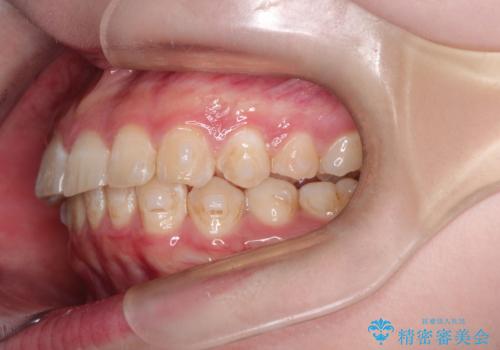

インビザラインで前歯のガタガタをきれいな歯並びへ

- 前歯のガタガタが気になるとのことで来院されました。

上顎の前歯の叢生があったのと、下あごの前歯が通常より1本欠損(先天欠損)していました。

上顎の歯と歯の間をわずかに削りスペースをつくり、並べる計画としました。インビザライン治療を選択されました。

しっかりとインビザラインを使用していただけたので、スムーズに治療を終了させることができました。